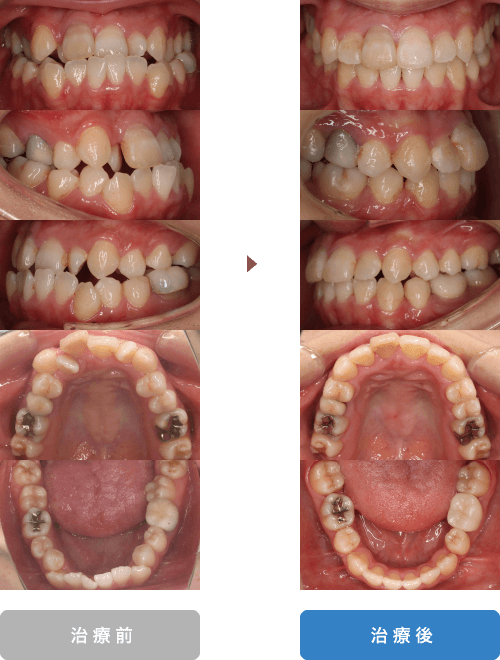

| 主訴 | 下の歯のガタガタと八重歯が気になる |

|---|---|

| 年齢 | 22歳 |

| 治療期間 | 2年6ヶ月 |

| 通院回数 | 15回 |

| 治療内容 | 上顎第一小臼歯の抜歯を行い、下の前歯のガタガタと上の八重歯の治療をマウスピース型矯正(インビザライン)にて治療を行いました。 |

| 抜歯部位 | 非抜歯 |

| 治療費 | 106万円(税込) ※処置料、保定料も含む |

| リスク、副作用 | 骨癒着などにより歯が動かない場合や、 矯正治療によって歯肉退縮する可能性があります。 |

| 担当医 | 長島歯科・矯正歯科 長島雄吾 |